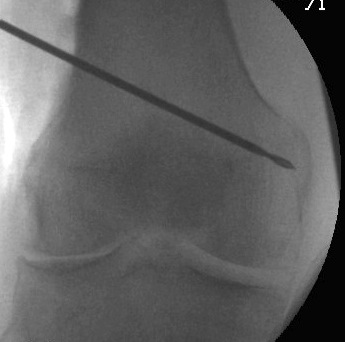

Osteotomy

- insert guide wires

- proximal lateral to distal medial

- proximal 1 - 2 cm above flare of lateral condyle

- aim towards adductor tubercle

- risk of medial hinge fracture reduced if osteotomy at or distal to adductor tubercle

- ensure these are perpendicular to the femoral shaft in the sagittal plane

- above patellofemoral joint and posterior condyles

- stop osteotomy 1 cm short of medial cortex